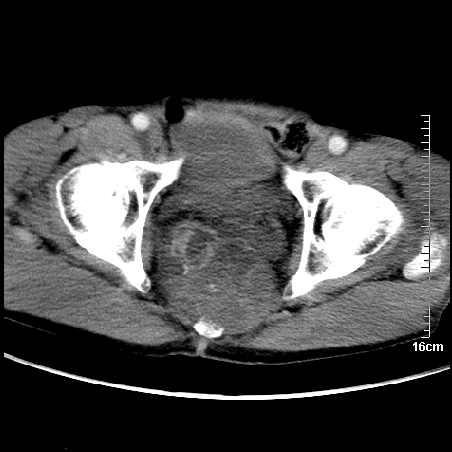

平扫:

部分骶尾骨已被软组织密度的肿瘤所取代,同意“首先考虑脊索瘤,不除外转移瘤”的意见。

1、骶尾部巨大软组织肿块,部分骶尾骨以被软组织肿块代替,呈不规则侵蚀;病变突向盆腔内;增强扫描病变呈不均质强化;首先考虑脊索瘤。不支持的一点就是病变内无钙化。